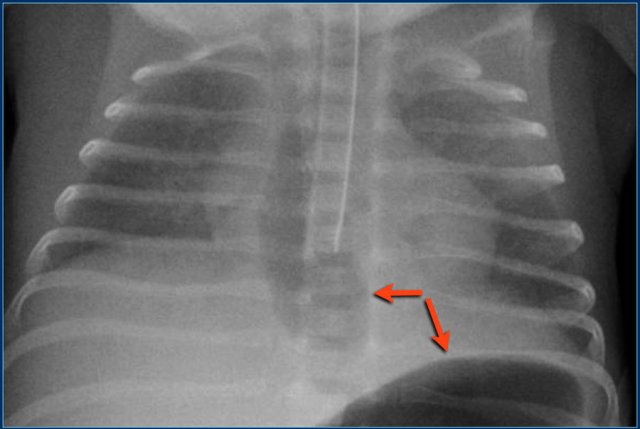

Chest drainage tube

Chest drainage tube are placed in case of respiratory distress caused by pleural fluid or pneumothorax in order to allow sufficient expansion of the lung for ventilation.

The tube should be positioned in the midaxillary line via the 4th - 6th intercostal space.

The position should be apical anterior in patients with a pneumothorax.

Study the image.

Then continue reading.

The findings are:

1. Endotracheal tube in good position.

2. Straight chest drain tube in good position. Drainage however is not optimal.

3. Mediastinal shift to the right. There is however no tension-pneumothorax, since the diaphragm has a normal convex upper border.

In this patient, who has a large pneumatocele, a pigtail catheter is placed in the pneumatocele.